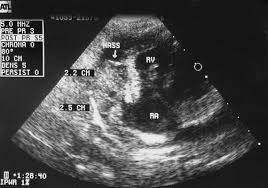

Dog Hemangiosarcoma Proven New Treatments That Prolong Life Pethelpful from images.saymedia-content.com When to euthanize a dog with hemangiosarcoma In fact, many dogs that are diagnosed with splenic hemangiosarcoma present to their veterinarian on an emergent basis with a history of lethargy, decreased appetite, weight loss, acute collapse, pale to white mucous membranes and/or swelling in their abdomen. Studies find that 1 out of 4 dogs with cancer of the spleen also have tumors on their heart. Stage 1 hemangiosarcoma in dogs. Common symptoms in affected dogs include abdominal pain, subnormal temperature, anorexia (appetite loss) and acute weakness. The vet tells you that your dog has cancer of the spleen and the spleen has ruptured. While it is less frequent compared to liver cancer, for example, spleen cancer can be seen in a number of cases. If the cause is from an injury, you will most likely know that your dog has internal injuries right away due to the swollen abdomen and sudden weakness or vomiting.

Studies find that 1 out of 4 dogs with cancer of the spleen also have tumors on their heart. When to euthanize a dog with hemangiosarcoma Due to its insidious nature, a ruptured spleen caused by a malignant cancer in dogs, is often nicknamed as the silent killer. veterinarian dr. Tumor is found only in the spleen. The spleen is a very important organ in the body and it plays important roles in rbc regulation and the immune system of the pet. What are the symptoms of spleen tumors in cats and dogs? Since dogs usually show only mild warning signs, cases of hemangiosarcoma may not be detected until the cancer has reached an advanced stage. — lump in the abdominal area Often, a tumor will rupture causing the spleen to bleed and resulting in an internal hemorrhage. If a dog has splenic hemangiosarcoma, it means the cancerous blood vessels are located in the tissue of your dog's spleen. Some of the symptoms that pet parents can be on the lookout for: It is a cancer made up of the cells that line blood vessels, and therefore can be found in any part of the body. Symptoms of dog spleen cancer are nonspecific;